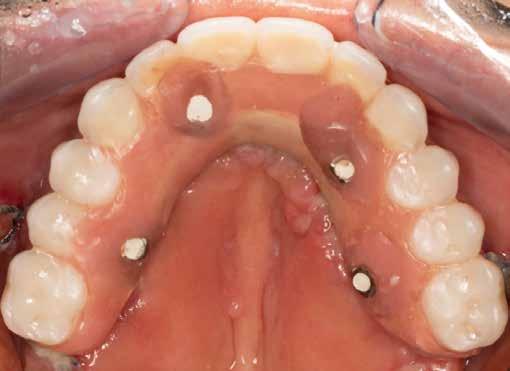

2. ábra: A maxilla preoperatív intraorális képe okkluzális nézetből.

5. ábra: Az All-on-4 hibrid protokoll alapján pozicionált implantátumok és multi-unit fejek intraorális, okkluzális nézetből.

6. ábra: Sebzárást követő okkluzális felvétel.